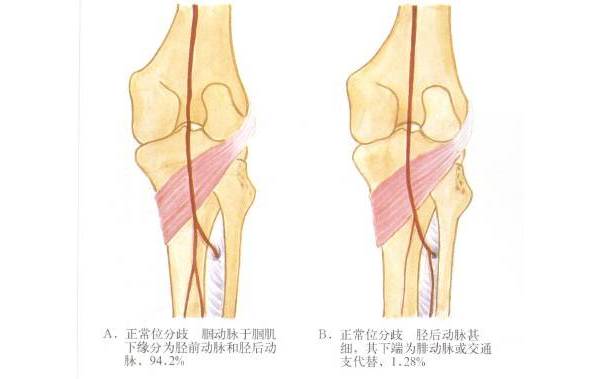

不要太把指背动脉当成动脉

指背动脉行程很短,而且纤细,在近节中段,就已经看不到,还不如指动脉近节背侧支明显。

解剖图谱更是理想化。